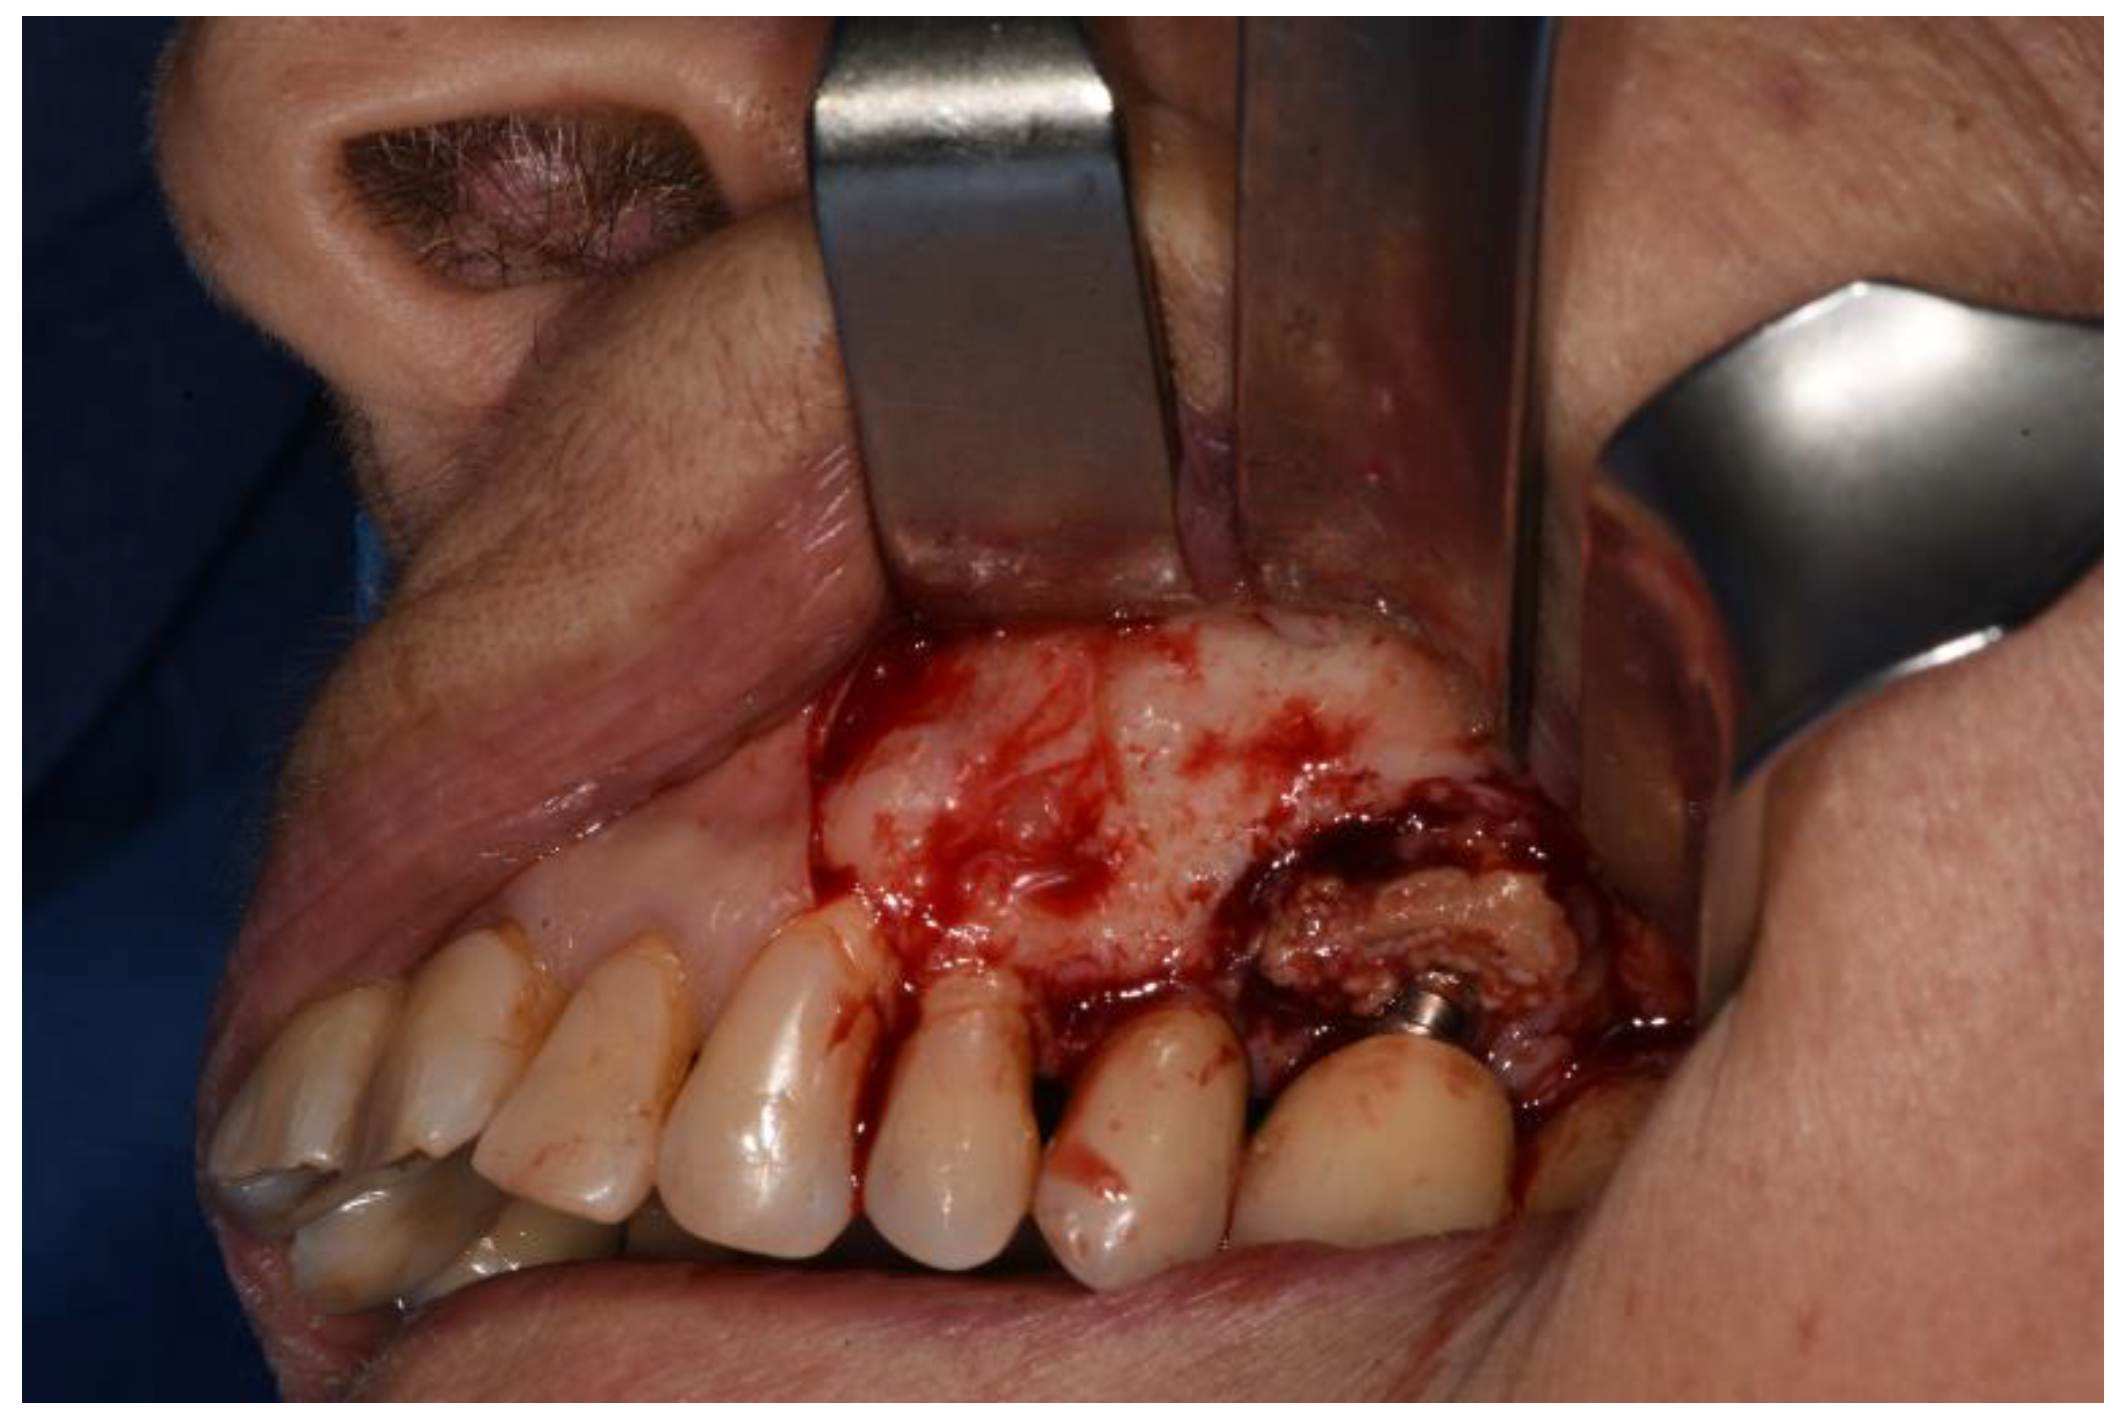

Figure 5. Osteotomy completed polipoid tissue in the maxillary sinus.